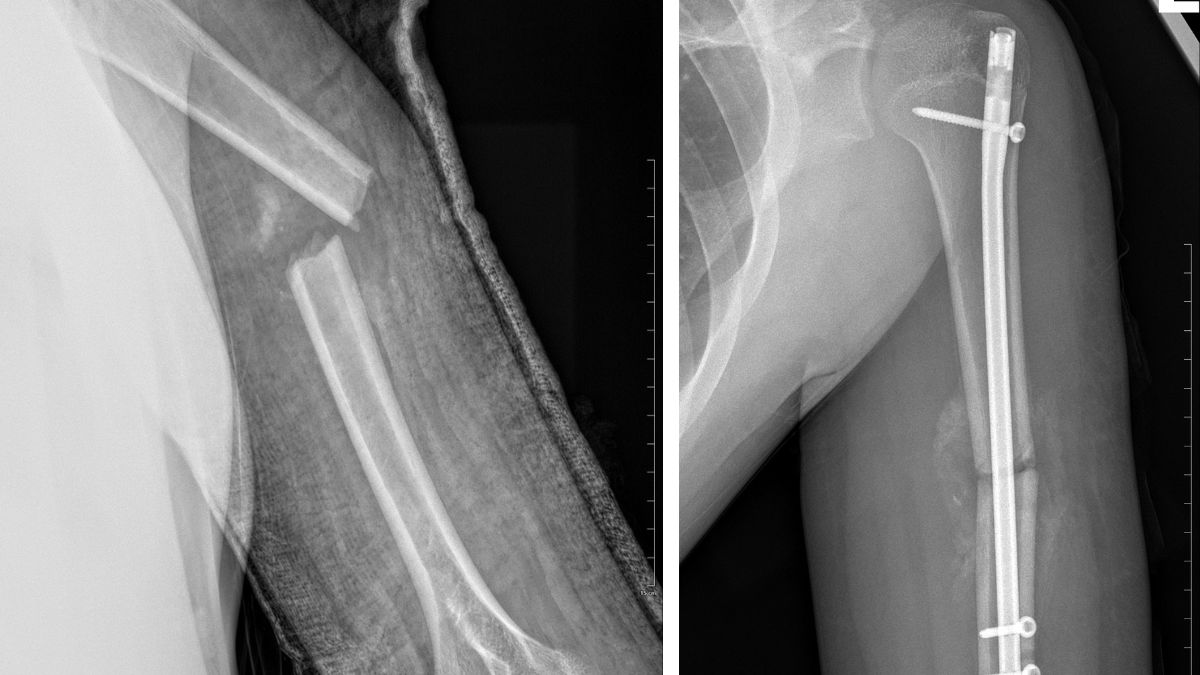

Завідуючий відділення Юрій Іванчук, лікарі травматологи Василь Данів та Василь Качур при переломах кісток гомілки, кісток передпліччя та плечової кістки проводять операції блокуючого інтрамедулярного остеосинтезу. Така методика дає можливість малоінвазивного остеосинтезу (через невеликі розрізи вводити фіксуючі стержні в канал кістки, які стабільно утримують перелом кістки).

“Які ж переваги даного методу? Це надійна стабілізація перелому, дуже рання реабілітація пацієнта, зменшення післяопераційного періоду та ускладнень, скорочення термінів перебування в стаціонарі. Дитина не потребує додаткової фіксації гіпсовими пов’язками та має можливість раннього навантаження та швидкого відновлення функціонування кінцівки”, – йдеться у повідомленні.

Раніше основним методом вибору лікування таких переломів був скелетний витяг. Це мінімум 1 місяць строгого незручного ліжкового режиму з цілодобовим доглядом за дитиною, з подальшою фіксацією гіпсовою пов’язкою з усіма незручностями від неї та значно подовженою реабілітацією пацієнта (до кількох місяців). Єдиним недоліком блокуючого остеосинтезу є вікове обмеження (дані операції проводяться у дітей віком від 10 до 18 років).